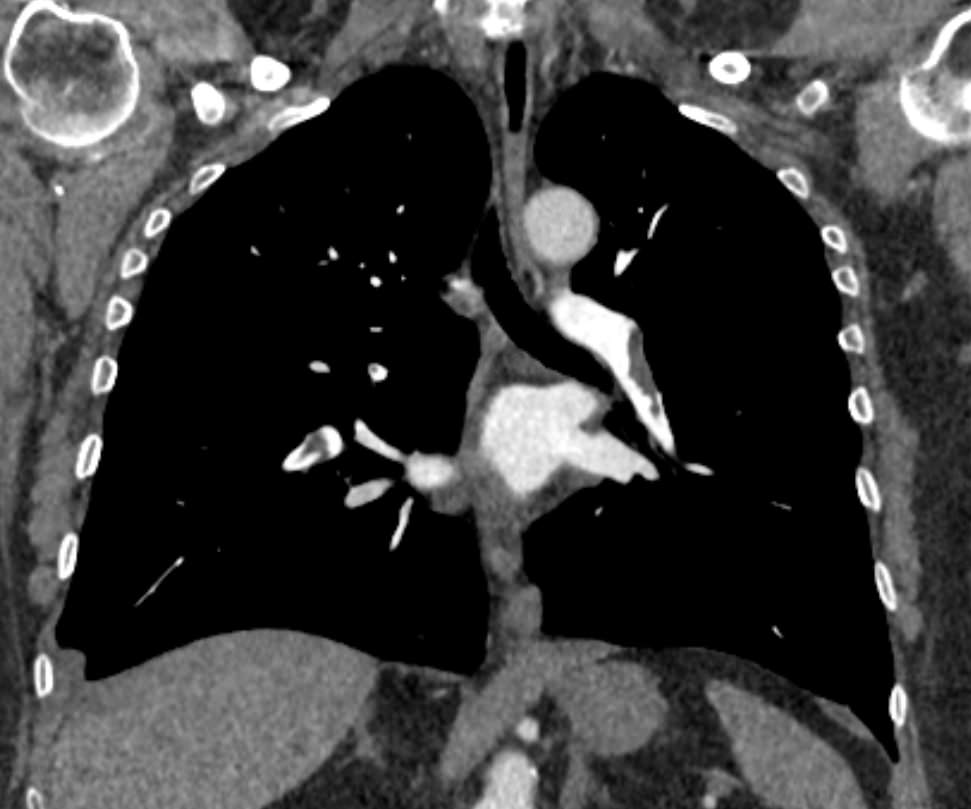

Наиболее информативным, при этом быстрым и неинвазивным (то есть без вмешательства в организм пациента), методом диагностики патологии легочной артерии является мультиспиральная компьютерная томография (КТ-ангиография). Методика основана на использовании рентгеновского излучения в сочетании с цифровой обработкой данных для получения трехмерных изображений сосудистой системы.

Для визуализации кровеносных сосудов в обязательном порядке применяется контрастное усиление. Для этого в вену пациента вводится йодсодержащий контрастный препарат, который попадая в кровоток активно поглощает рентгеновские лучи и ярко контрастирует сосудистую систему, в том числе легочной артерии, на фоне окружающих тканей. Использование контраста дает возможность визуализировать даже мелкие артерии и выявить патологию.

В наших диагностических центрах КТ-ангиография легочной артерии проводится на современных мультиспиральных компьютерных томографах экспертного уровня TOSHIBA AQUILION. Оснащение аппаратов позволяет получать детальные снимки и трехмерные изображения сосудистой системы легочной артерии, при этом применение скоростной мультисрезовой методики сканирования значительно снижает уровень лучевой нагрузки на пациента.